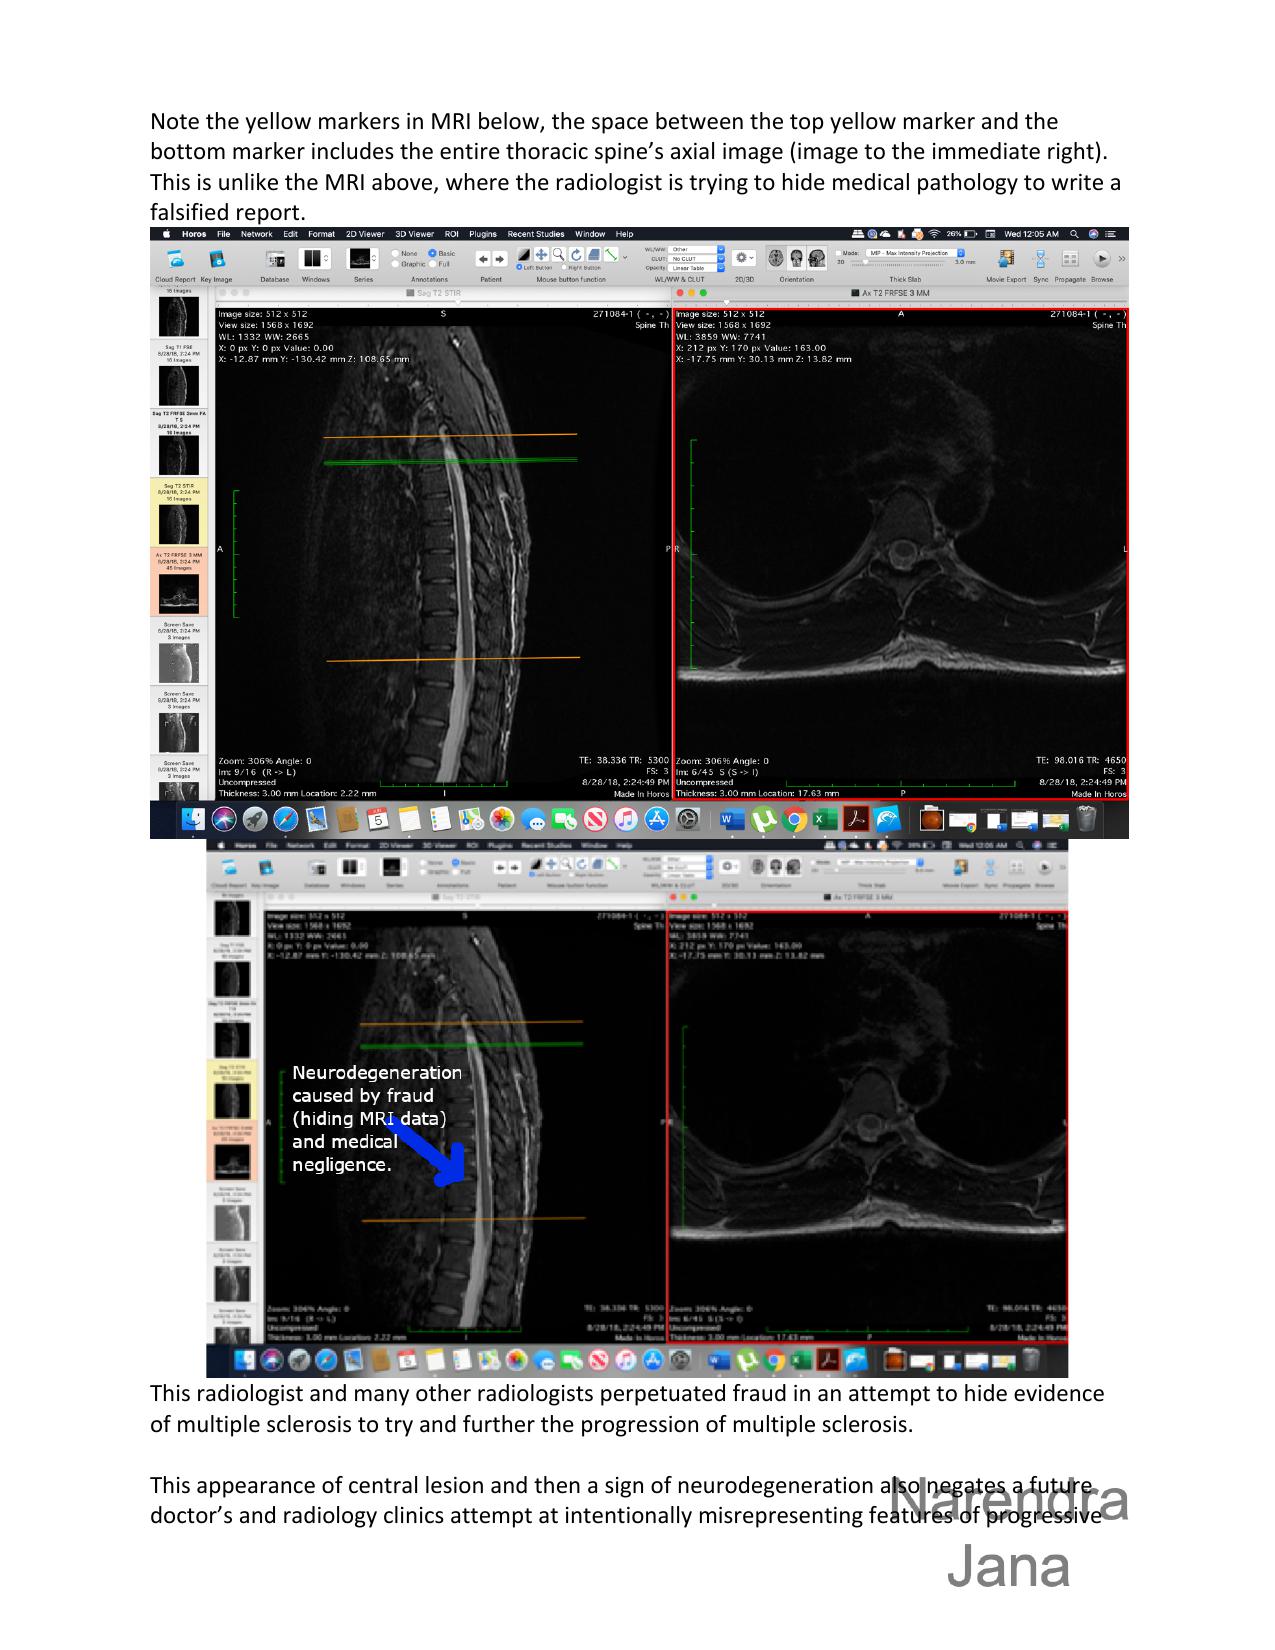

3.     3. The central lesion evolves to neurodegeneration, which Dr. Pia Schumacher tries to intentionally misstate as "disk" degeneration of the spine, which is aburd. The neurodegeneration can be clearly seen in the next MRI and many other MRIs. It's a central region of demyelination that evolves to neurodegeneration of the spinal cord. The radiologist is trying to hide progress in the clinical condition and Dr. Pia Schumacher is harming the patient by trying to create new lesions to create progress to physical disable the patient:

So since there is clear evidence of fraud in one setting that evidence of fraud is also easy to apply to the falsified statement of Dr. Pia Schumacher. What is stated by Dr. Schumacher as "protrusions" or "disk" degeneration are really a features of neurodegeneration intentionally mistated by Dr. Schumacher to perpetuate medical neligence and assault in this medical setting.

These features of neurodegeneration only occur from repeated inflammatory episodes (due to multiple sclerosis) that take place in the central spinal canal (which is what the radiologist in this video is trying to hide) not the skeletal system. These features only occur due to long term neurodegeneration from long term conditions like progressive Multiple Sclerosis. Thus I have progressive multiple sclerosis.